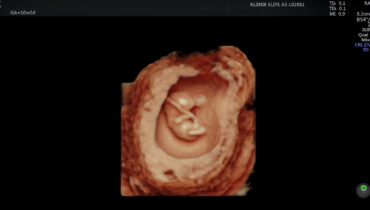

Gynecology deals with the study, diagnosis and treatment of diseases of the female reproductive organs, menstrual disorders, pregnancy and menopause-related conditions. Gynecologists also deal with preventive medicine and the treatment of, for example, cervical and ovarian cancer, endometriosis, cysts, inflammation, hormonal disorders and sexually transmitted diseases. Gynecology also includes prenatal care and pregnancy monitoring, as well as postpartum recovery. Elite Clinic offers a variety of gynecological procedures and surgeries.